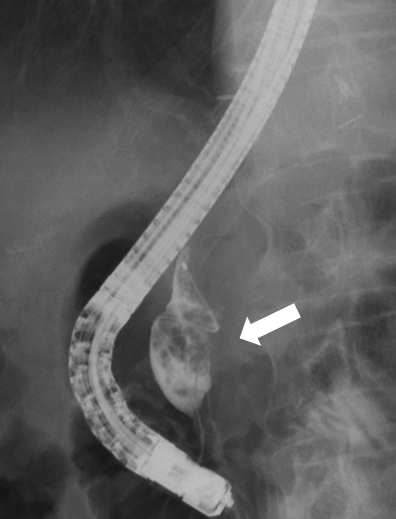

ERCP所見:胆管造影で,膵内胆管に充満する乳頭状の約2 cmの腫瘤影を認めた(Fig. 6).乳頭からの粘液の排出は見られなかった.腫瘤の生検では,高分化腺癌が検出された.

ERCP demonstrated a 4 cm papillary mass in the remnant distal bile duct (second tumor).